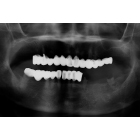

傳統植牙能取代損失的牙齒,但治療過程漫長痛苦,全口無牙的患者,如需製作固定義齒,每一個牙弓至少需8-10顆植體,有些牙脊萎縮嚴重的位置,可能需許多複雜的補骨過程,對於忙碌與年老的患者,是體力與時間的大負擔。

利用4-6顆植體及類似造橋的力學設計原理,將力量平均分配,使得傳統需要8-10顆植體才能支持的整排假牙,現在只須4-6顆植體即可達成。而且手術時間短,復原快速,如植體穩定性高,幾天之內患者就能恢復正常咀嚼。

圖1